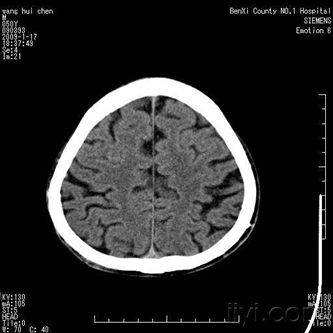

1.下列哪種方法為顱腦疾病診斷的基本方法: ( )

A.腦室造影 B.計(jì)算機(jī)體層 C.頭顱平片 D.醫(yī)學(xué)影像 E.腦血管造影